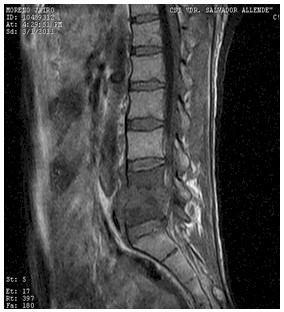

Presentacion de un caso clinico. Discitis por resonancia magnetica por imagenes .2

Secuencias T1 sagitales:

Secuencias T2 sagitales: